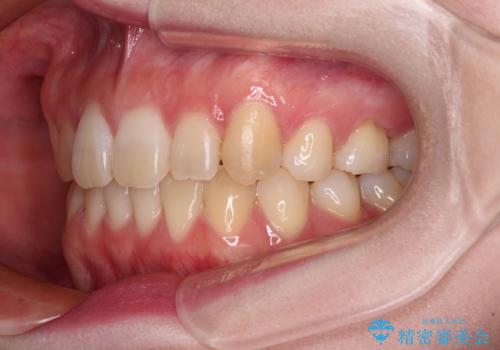

ディープバイトをインビザライン矯正で改善

- 前歯のデコボコと強い咬みしめを気にして来院された患者様です。

インビザラインを用いて、前歯の叢生を解消するとともに、ディープバイトを改善していくこととしました。

上顎に乳歯が左右1本ずつ残っていたため、若干咬み合わせに不具合が残りましたが、強い咬合力の原因であったディープバイトをしっかりと改善することができました。